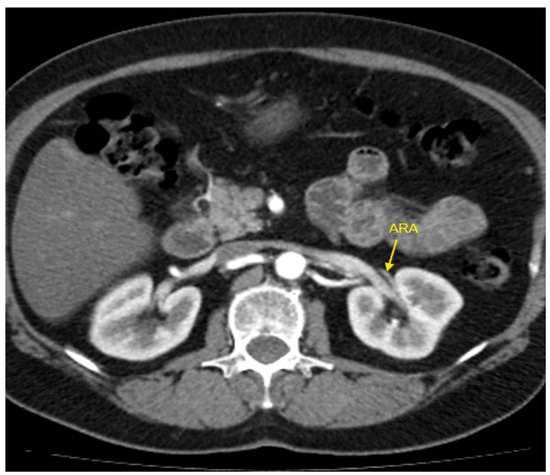

Figure 1, Figure 2, Figure 3, Figure 4 and Figure 5 show examples of some renal vascular abnormalities we identified in our study population.

Figure 2. Contrast-enhanced CT imaging of a 47-year-old female patient with refractory hypertension revealed an accessory renal artery in the left kidney, shown by the yellow arrow. ARA—accessory renal artery; CT—computed tomography.